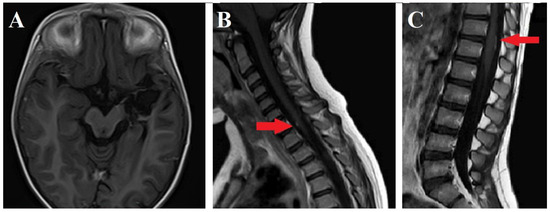

2. Case Report